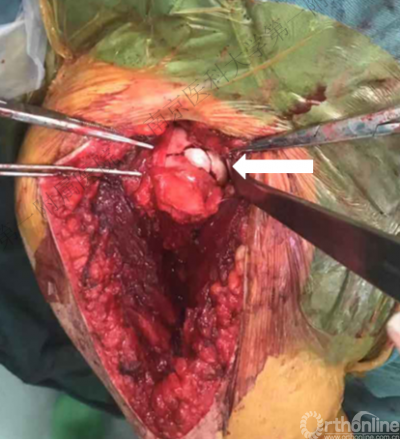

盂肱下韧带肱骨侧止点撕裂

切开部分肩胛下肌后于肩胛盂前方插入骨撬,帮助显露反Hill-Sachs损伤。

1.外旋肱骨头,显露肱骨头关节面损伤处。